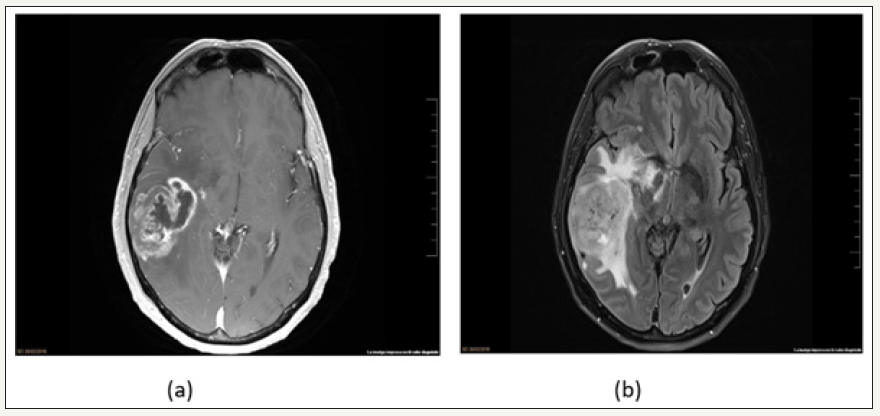

The brain MRI showed a right temporal neoplasm with areas of central necrosis, neo-angiogenesis and irregular contrast enhancement. The perfusion study showed an increment in the relative cerebral blood volume. The spectroscopic analysis demonstrated increment of the Cho peak, Cho/Cr ratio, Cho/NAA ratio and Lip/lac peak. All these findings were compatible with glioblastoma (GBM) (Figure 2). Complete mass excision under general anesthesia and neuro-navigation system was performed without complications. Post-operative course was uneventful. Anathomopatological examination demonstrated a GBM, grade IV of the World Health Organization (WHO) classification, wild-type Isocitrate dehydrogenase 1(IDH) and ATRX, nonspecific p53, and mild-immunoreactivity epidermal-growth factor receptor (EGFR) with methylated O6-methylguanine–DNA methyltransferase (MGMT). He was discharged, and he started concomitant adjuvant treatment with temozolomide and radiotherapy.

figure 2: Axial T1 with contrast and axial FLAIR brain MRI showed a right temporal expansive tumor, with central necrosis, angiogenesis, heterogeneous enhancement and vasogenic edema.